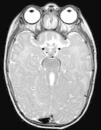

The first case corresponds to a 6-month-old female infant with psychomotor delay and axial hypotonia, vertical nystagmus and erratic eye movements. Cerebellar vermis hypoplasia had been suspected before birth. The postnatal brain MRI revealed the complete absence of the cerebellar vermis with abnormal cerebellar peduncles and a fourth ventricle with the “molar tooth” sign (Fig. 1). Joubert syndrome (OMIM 213300) was confirmed by the detection of the homozygous mutation c.2168G>A (pArg723Gln) in the AHI1 gene. The syndrome is characterised by the congenital malformation of the brainstem and agenesis or hypoplasia of the cerebellar vermis, causing hypotonia and ataxia, delayed motor development, nystagmus, and a tachypnoea/dyspnoea breathing pattern in the neonatal period. Cognitive deficits occur in varying degrees. It can be associated to retinal dystrophy, nephronophthisis and polydactyly, which occur in other ciliopathies. It follows an autosomal recessive inheritance, and mutations in different genes have been identified: AHI1, NPHP1, CEP290, TMEM67, RPGRIP1L, ARL13B and CC2D2A.5 Bardet–Biedl syndrome, Meckel–Gruber syndrome, Leber congenital amaurosis and nephronophthisis share mutations in the CEP290 gene, demonstrating the genetic and clinical overlapping of syndromes associated to a primary ciliary dysfunction.6